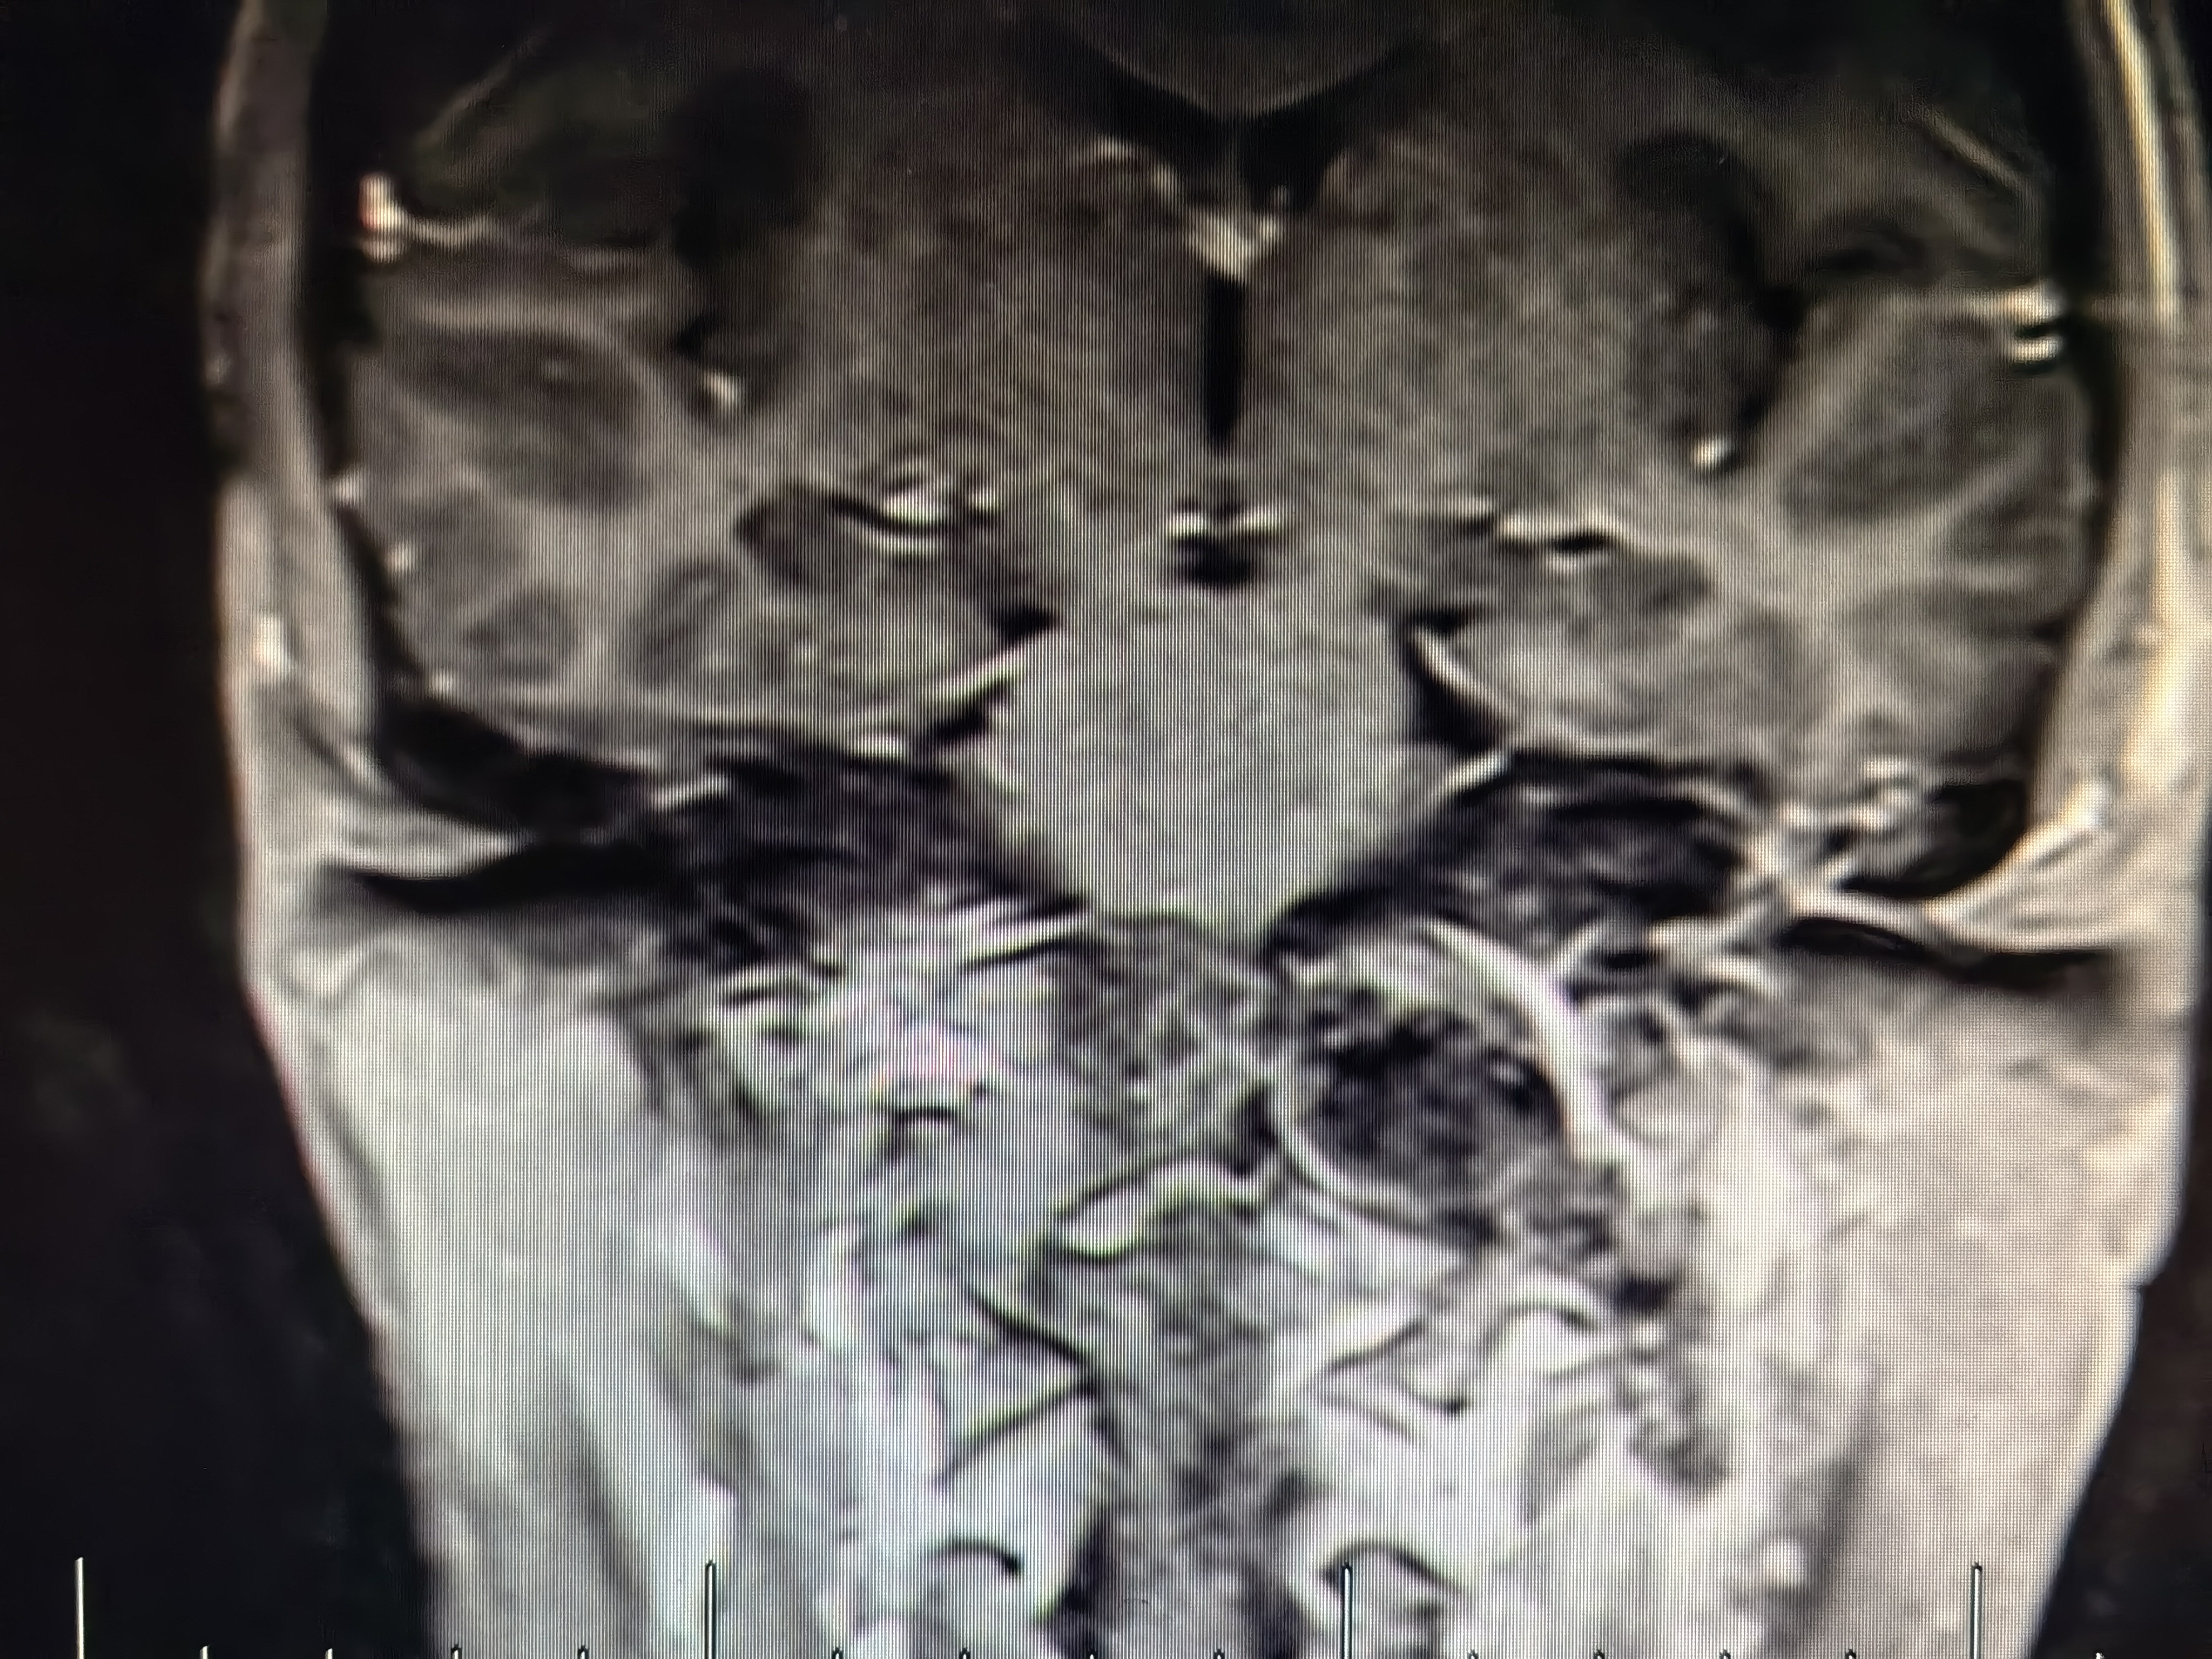

术前磁共振